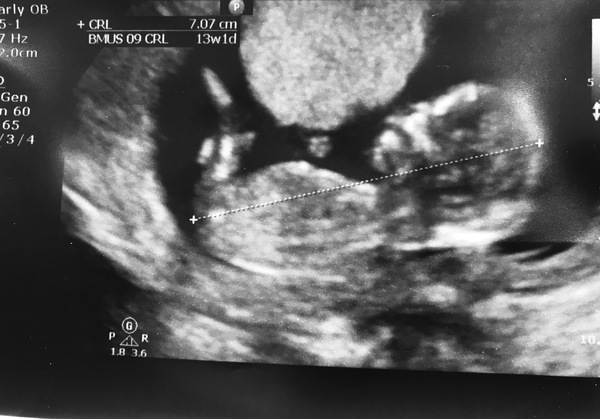

Shook2018 · 01/03/2018 19:04

What do you think guys? Nub and light looking inconclusive/looking like a boy to me?!

I'd guess a boy for you @Shook2018

Shook2018 · 01/03/2018 20:04

So exciting! This has also definitely confirmed for me that I'll be finding out - too excited even over a theory to wait until the end!